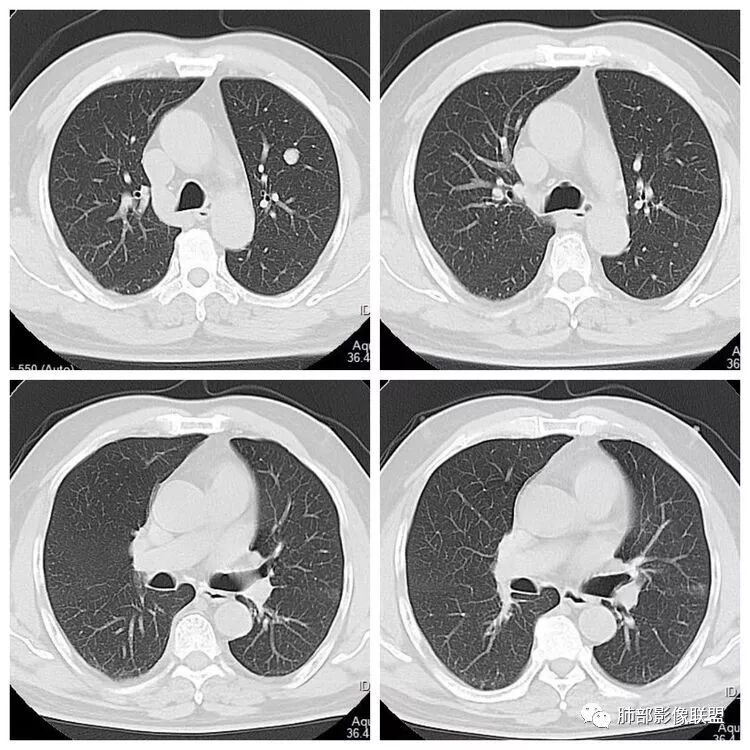

左下叶内前基底段实性占位堵塞支气管,强化较弱,考虑肺癌可能 ,小细胞?腺癌?

患者老年男性,“左肺占位”收入住院。查CEA轻度升高。胸部CT:左肺肺门占位并左肺下叶阻塞性,远端肺组织膨胀不全,增强可见轻度强化,内似见低密度灶。双肺多发类圆形结节,以左肺上叶尖后段为大,内可见部分钙化,边缘光滑、清楚。综合考虑恶性病变,鳞癌并转移可能大,鉴别腺癌、结核。

胸CT:左下叶内前基底段肿块,支气管堵塞,强化弱,延迟强化,两肺多处结节,右上肺门淋巴结大。常规考虑:肺癌可能 ,肺内小结节,转移?鉴别:错构瘤,TB等。

左肺下叶占位,左肺下叶前内支气管阻塞可疑(缺乏薄层),病灶有膨胀性,远端较内侧细,增强病灶强化不明显——乏血供病灶,病灶沿支气管生长,考虑恶性病变,左肺上叶可见小结节病灶,边缘光滑清晰,考虑转移瘤,综上所述考虑恶性病变,左肺下叶小细胞类癌可能,左肺上叶转移。

左肺下叶结节支气管进入截断,远端肺不张,增强后坏死不均匀,肺癌明显,至于病理类型,鳞癌,小细胞,腺癌都有支持和不支持的地方,个人倾向于鳞癌可能,理由,纵隔淋巴结肿大不明显,远端阻塞性不张,支持小细胞的地方,坏死呈沼泽样,但纵隔无明显淋巴结肿大及冰冻表现。腺癌这种表现一般为低分化腺癌,但远端阻塞性不张及纵隔无明显淋巴结肿大不支持。

1.主病灶明显堵塞支气管,我觉得如果结核爬行,应该是外向内爬,这个我觉得是内向外堵塞,而且爬行的结核一般是肉芽肿,不是坏死,增强不会这么低,这个密度和强化比较符合一个坏死。最重要鉴别,结核的爬行是外向内,周围有树丫。这个是内向外,支气管堵塞且坏死明显,外周的堵塞性肺不张,没有树丫,所以主病灶考虑内向外,故结核爬行不太符合。而中央型腺癌不是没有,而是少,加上坏死这么明显,淋巴结转移不明显,故猜测鳞癌或者唾液腺肿瘤可能性比较大,因为后者也是支气管中央起源,强化比较弱的。腺癌和小细胞不太典型,类癌可以表现为支气管粘液栓,但是强化不够。

1.定位:左肺块影同时累及下舌段及下叶内基底段且相互延续。病灶跨叶,或存在叶裂发育异常,或者说就是病灶的肺门蔓延。

2.病灶前上部分与舌段支气管相关且形成阻塞。

6.分析:男性患者,左肺门区块状影,支气管阻塞,强化不显著,未见淋巴结肿大,更多见于肺鳞癌。难以解释的是下肺病灶的生长方式。